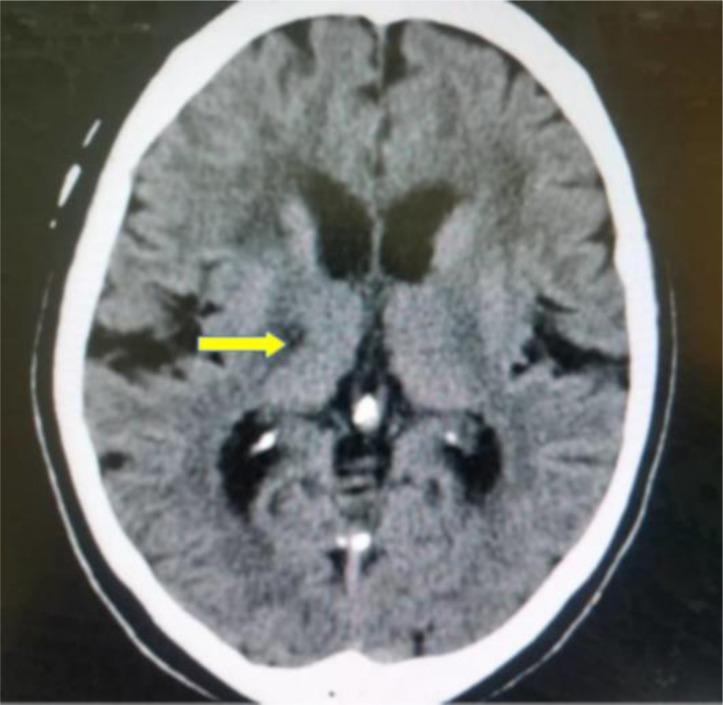

Computed tomography patterns of intracranial infarcts in a Ghanaian tertiary facility.

About 50.6% of the study participants were females with an average age of 62.59±13.91 years. Males were affected with ischaemic strokes earlier than females (0.001). The risk factors considered were, hyperlipidaemia (59.5%), hypertension (49.0%), Type 2 diabetes mellitus (DM-2) (39.6%) and smoking (3.0%). The three commonest ischaemic stroke CT scan features were wedge-shaped hypodensity extending to the edge of the brain (62.8%), sulcal flattening/effacement (57.6%) and loss of grey-white matter differentiation (51.0%), which were all significantly associated with hypertension. Small deep brain hypodensities, the rarest feature (2.2%), had no significant association with any of the risk factors considered in the study.

约 50.6%的研究参与者为女性,平均年龄为 62.59±13.91 岁。男性比女性更早受到缺血性中风的影响(0.001)。考虑的危险因素有高脂血症(59.5%)、高血压(49.0%)、2 型糖尿病(DM-2)(39.6%)和吸烟(3.0%)。三种最常见的缺血性中风 CT 扫描特征是楔形低密延伸至脑边缘(62.8%)、脑沟变平/消失(57.6%)和灰白质分界丧失(51.0%),这些都与高血压有显著关联。最小的深部脑低密灶是最罕见的特征(2.2%),与研究中考虑的任何危险因素都没有显著关联。